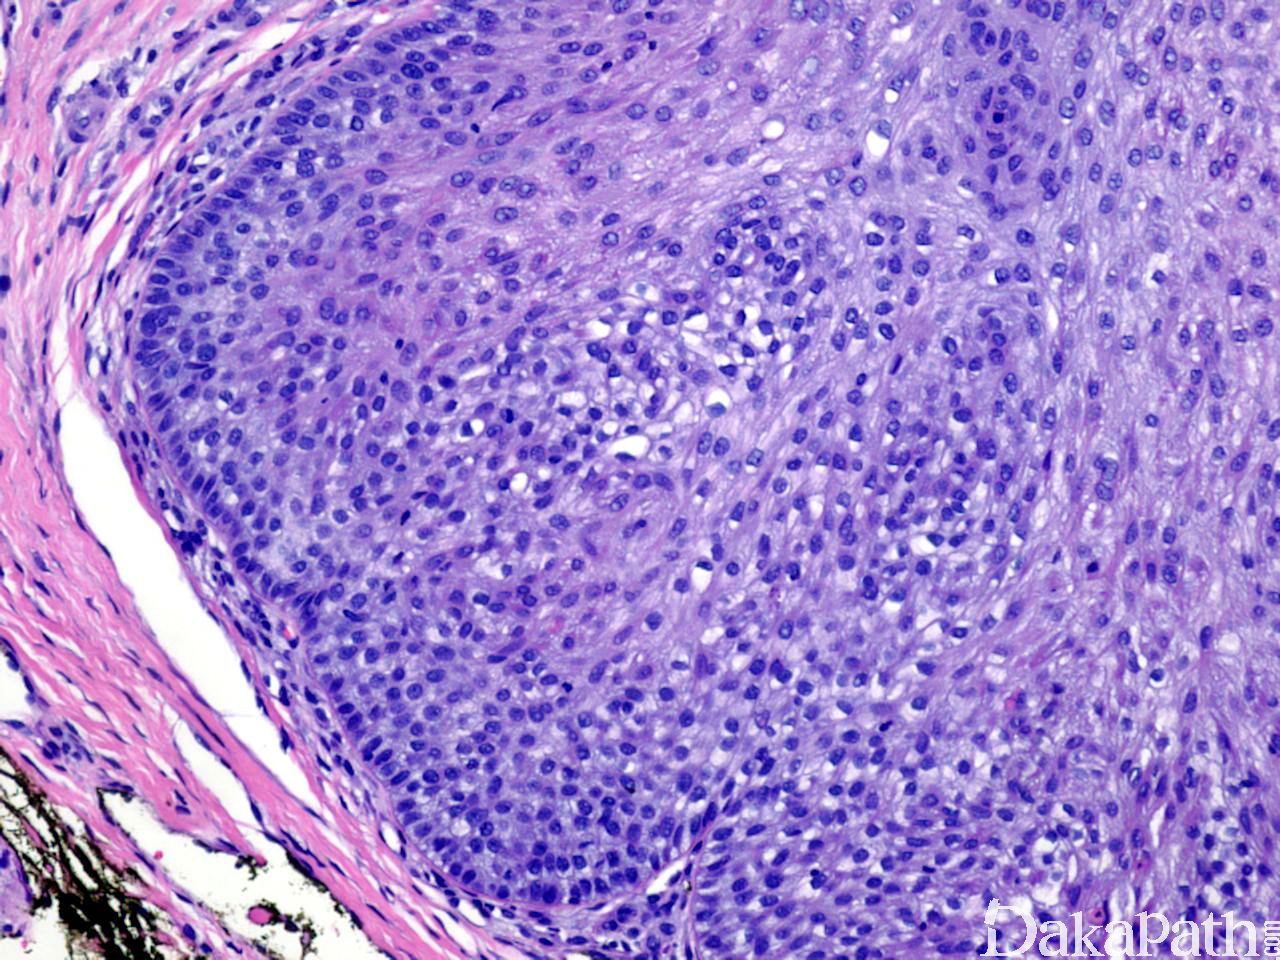

瘤体小而界限清楚,由一个或多个小叶构成,典型者常由小的外生性成分和延伸至真皮网状层上部的内生性成分组成;

小叶往往有数处与表皮或毛囊漏斗相连,小叶周边是一层柱状基底细胞样的细胞,核栅栏状排列,似外毛根鞘;

周围常围绕一层嗜酸性玻璃样变、带有折光性、增厚的基底膜样物质;

细胞呈立方形,胞核圆、居中,胞质淡嗜酸性或透亮;

可出现角化和鳞状旋涡;